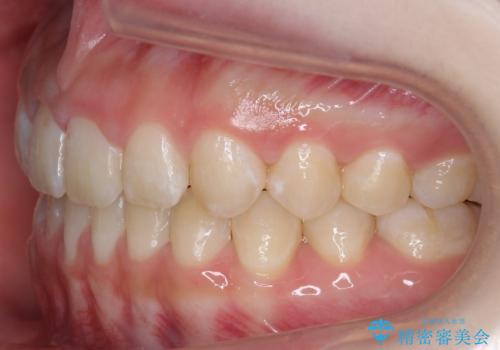

隙間を閉じる際、奥歯が倒れたため、途中ワイヤー矯正を併用しています。

上の前歯の隙間を閉じながら前歯を後方に下げているため、口元もひっこみ、口が閉じやすくなりました。